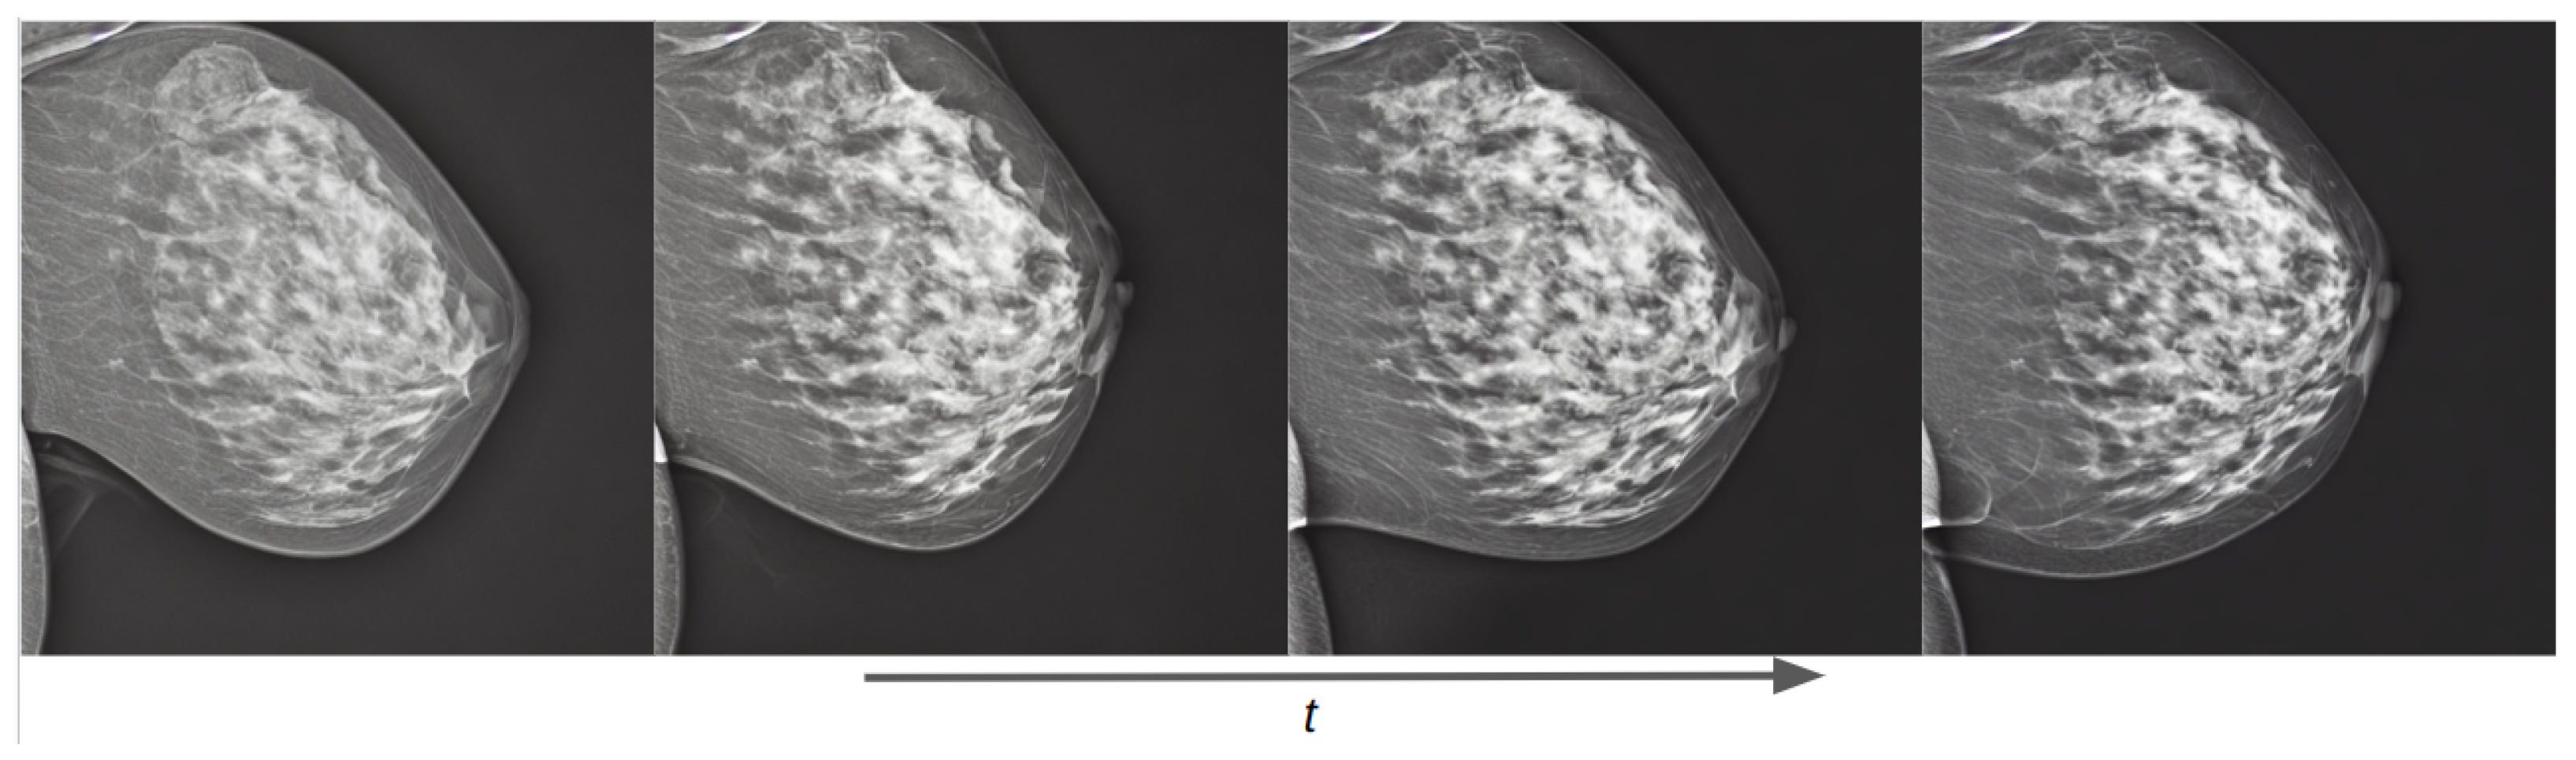

Figure 14.

Training evolution of the diffusion process on a conditional pretrained model trained with Siemens images at epochs 1, 3, 6, and 10. The prompt is: “a mammogram in CC view with high density”.

Training examples of the two separate conditional models using prompt text are shown in Figure 13 for the OMI-H dataset and Figure 14 for the VinDr dataset. We observe that the fine-tuning technique allows the generation of meaningful images from epoch one. For the Hologic example, we can observe that, as the training process increases, the mammogram reduces its shape in accordance to the area described in the prompt text. Moreover, it can be noticed that our models differentiate the overall intensity appearance of mammograms, which is different between Hologic and Siemens systems.

Thanks to the combined fine-tuning of the CLIP text encoder and the UNet weights, our conditional models can learn the anatomical structure and form of a mammogram, and can also push the generated image in the direction of the text prompt semantics as the training process increases.